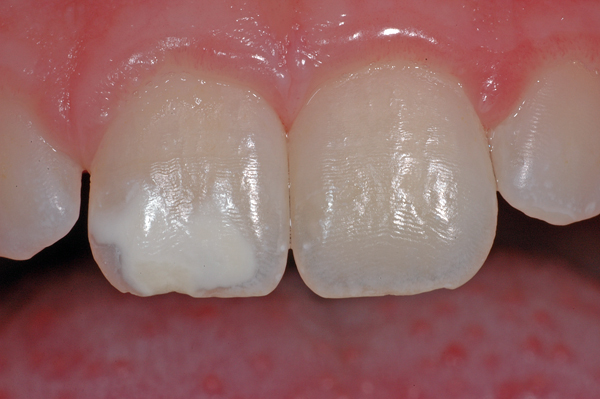

In diesem Beispiel ist ein «weisser» Fleck auf dem rechten oberen Schneidezahn (Zahn 11) einer 7-jährigen Patientin zu sehen. Solche Flecken sieht man häufig, z.B. wenn im Kleinkindalter ein Sturz auf die Milchzähne erfolgt ist und dabei die Wurzeln der Milchzähne die Zellen, die den bleibenden Zahn bilden, in Ihrer Funktion beschädigen. Aber auch andere Ursachen sind möglich, meist lässt sich aber nicht genau sagen, weshalb der Fleck entstanden ist.

Der Zahn ist allerdings, abgesehen von einer ästhetischen «Einbusse», vollkommen in Ordnung und braucht keine Therapie. Ästhetische Korrekturen sind möglich, sie werden individuell nach Bedürfnissen und Möglichkeiten geplant.

Im Bild sind zudem feine Querrillen auf den Zähnen zu sehen. Diese Rillen heissen Perikymatien und sind völlig «normal»

Sie sind vor allem an frisch durchgebrochenen, jungen Zähnen gut sichtbar. Die Ausprägung kann von Person zu Person verschieden stark sein.

Im Laufe des Lebens verflachen und verschwinden diese Rillen meist durch den Verlust von Zahnschmelz.

- Weisser Fleck auf dem rechten oberen Schneidezahn (Zahn 11) einer 7-jährigen Patientin